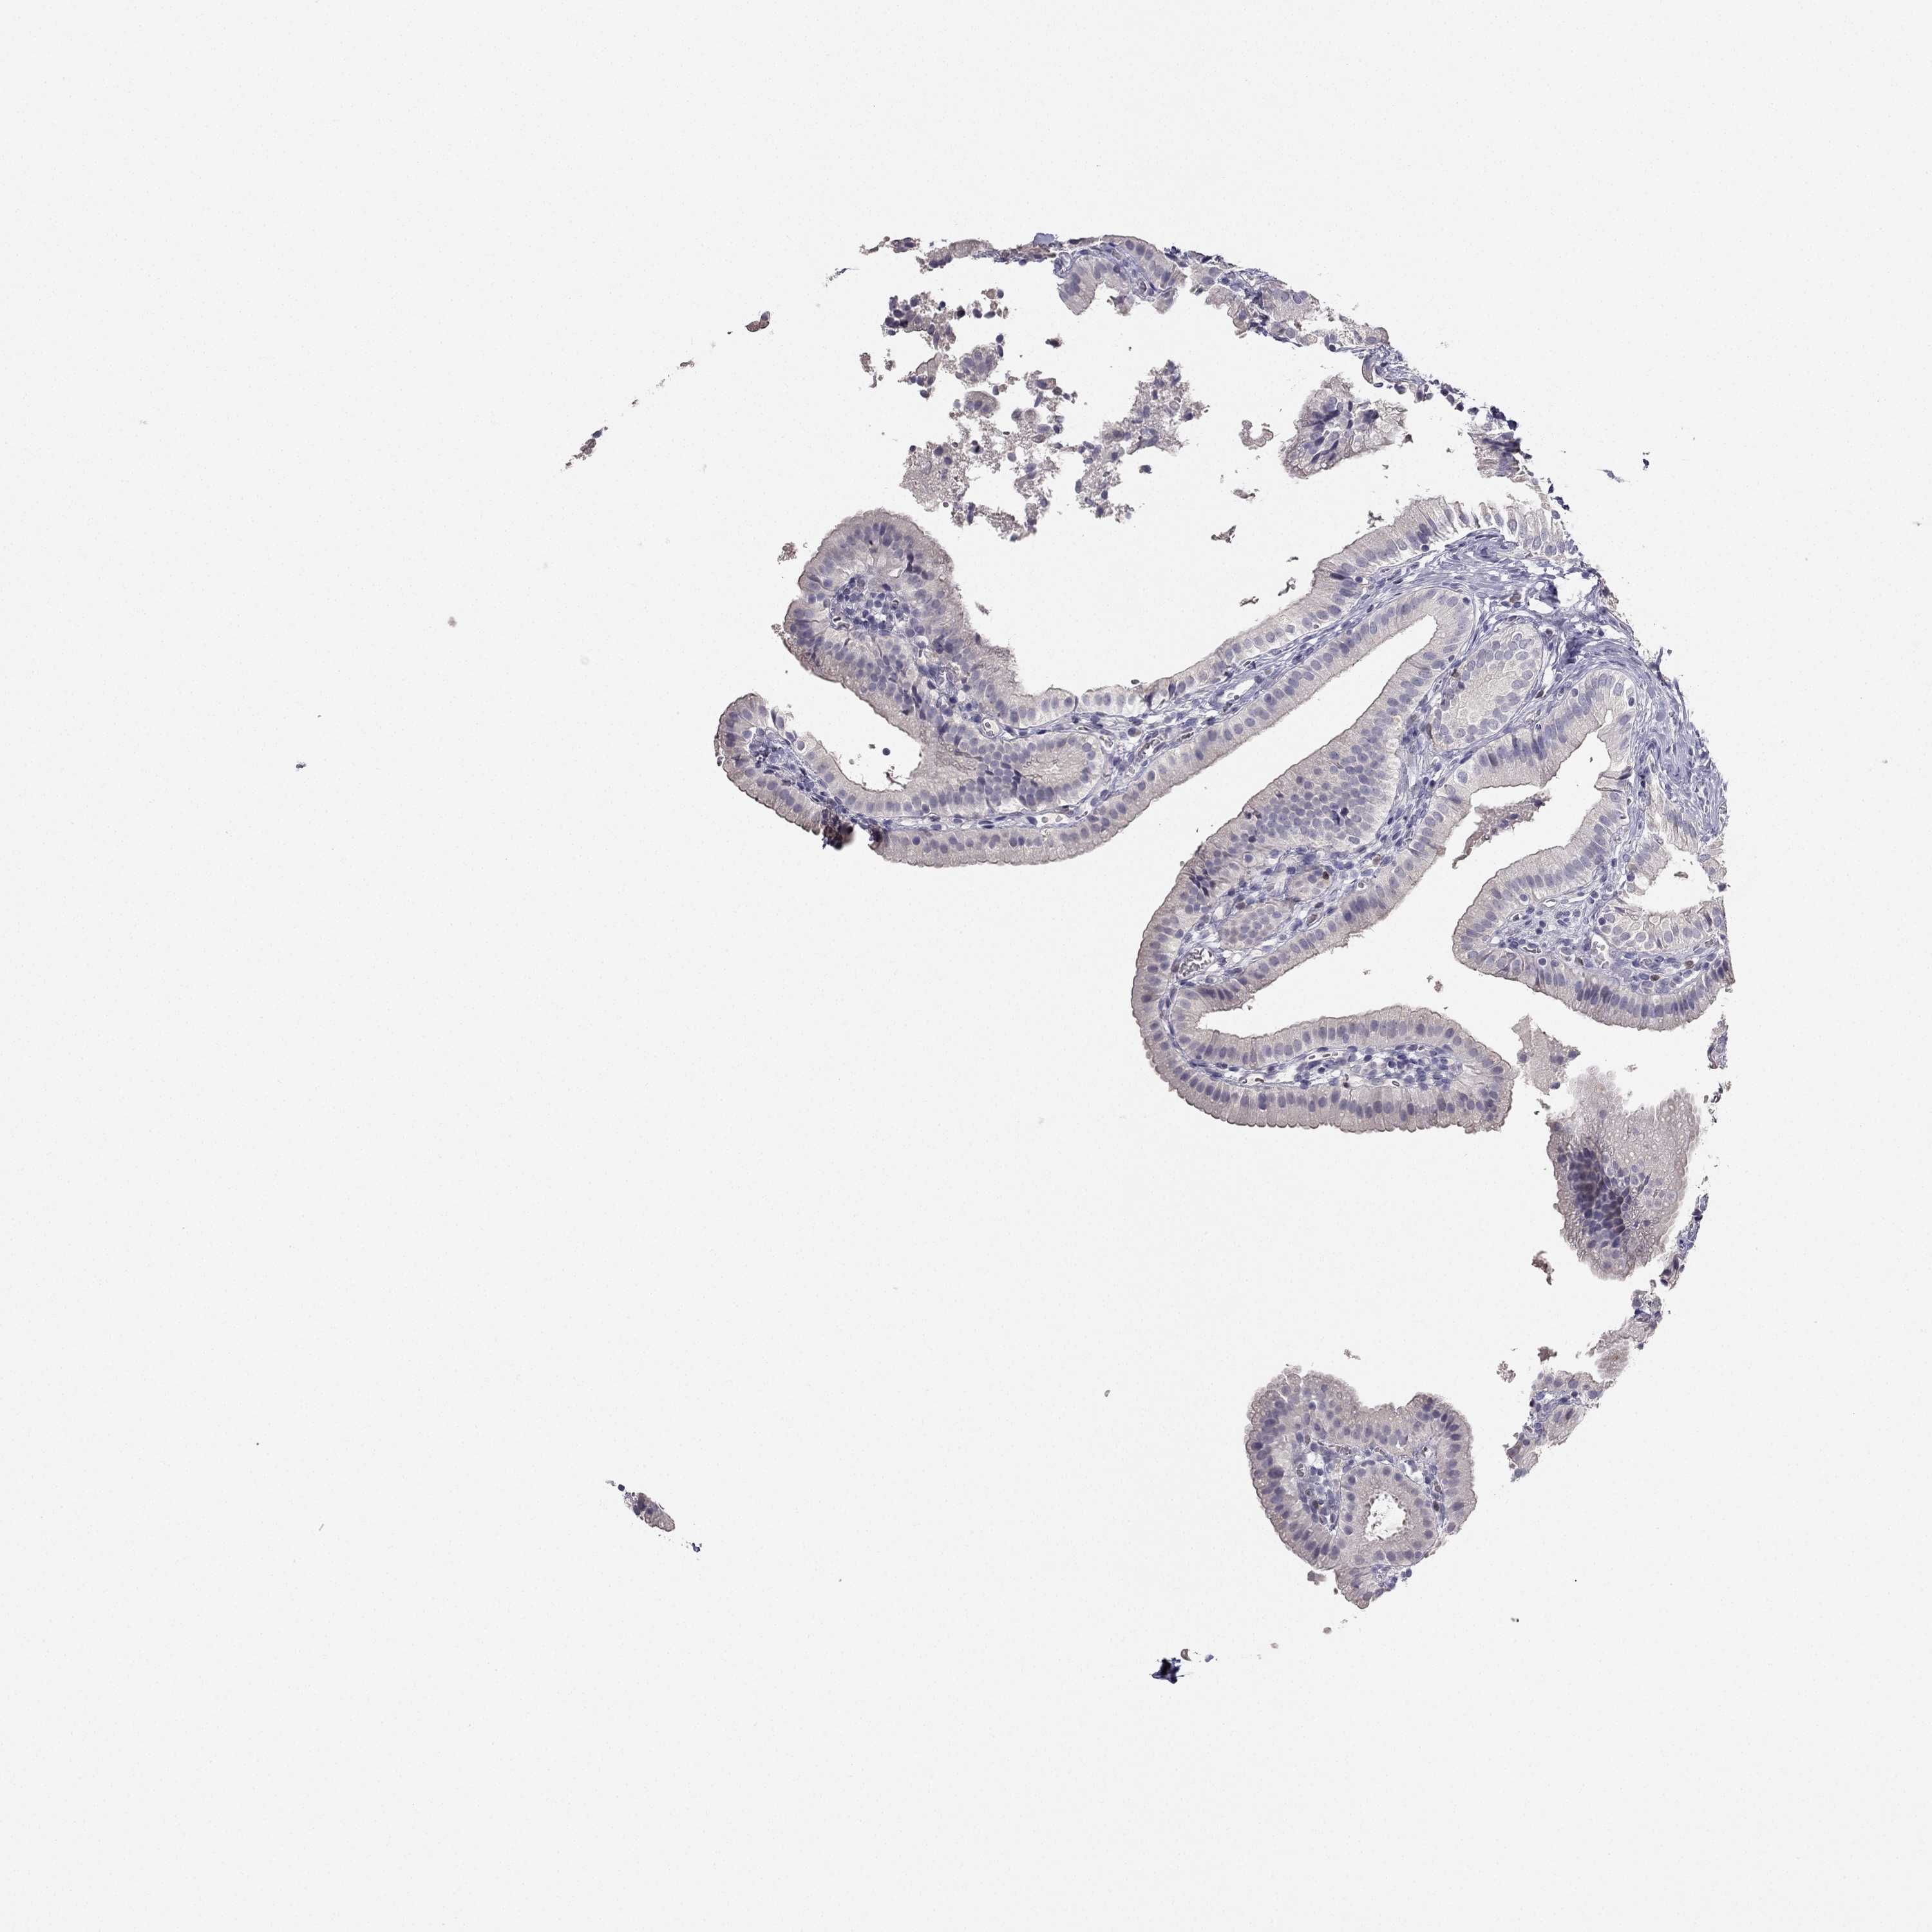

TISSUE PRIMARY DATA GALLBLADDER Show tissue menu

GALLBLADDER - Antibody stainingi

Antibody staining in the annotated cell types in the current human tissue is reported as not detected, low, medium, or high, based on conventional immunohistochemistry profiling in selected tissues. This score is based on the combination of the staining intensity and fraction of stained cells.

Each image is clickable and will lead to virtual microscopy that enables deeper exploration of all samples and also displays staining intensity scores, fraction scores and subcellular localization as well as patient and tissue information for each sample.

Antibody HPA007305Antibody HPA007306Antibody CAB000106

Glandular cells MediumMediumNot detected